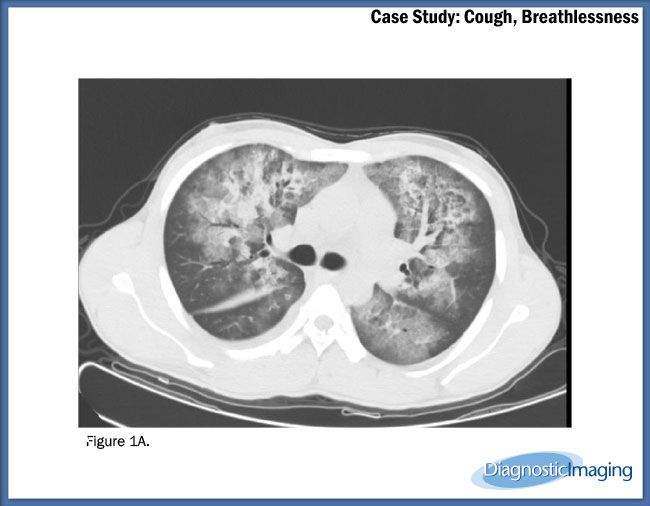

Case History: 22-year-old patient presents with cough and breathlessness.